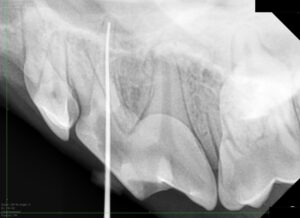

全身麻酔下で詳細な検査を行います。歯科レントゲン撮影を行い、現時点ですでに歯の根の周囲に異常がないか、他にも歯周病の進んだ歯が無いかなどを確認します。

検査後、麻酔を維持したまま実際の治療に進みます。歯内治療では歯の中の感染を起こした歯髄を専用の器具を使って取り除きます(抜髄)。

歯髄を取り除いて内部を洗浄した後、再度細菌が増殖するスペースを残さないように詰め物を入れます(根管充填)。